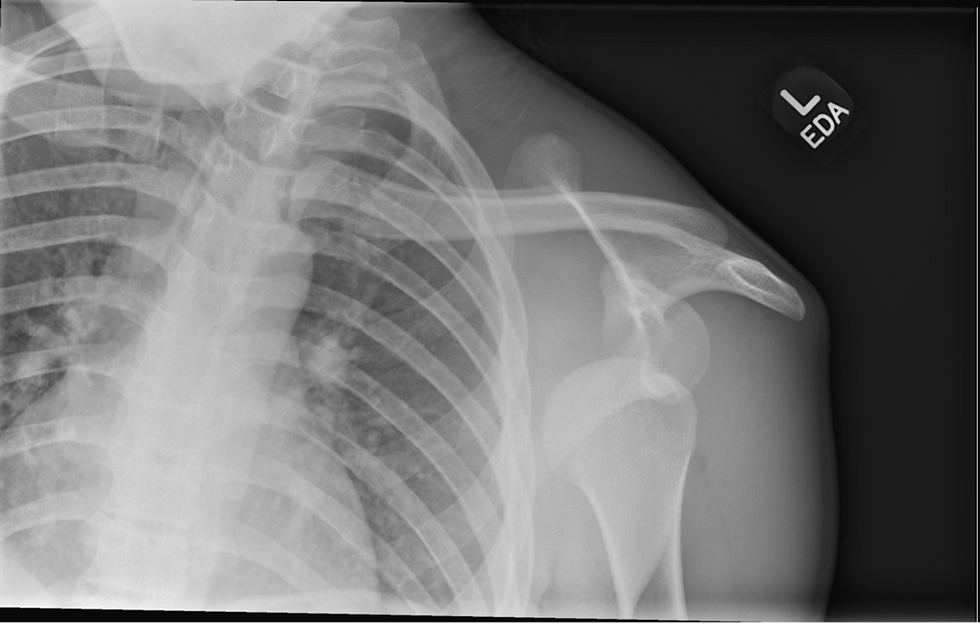

Initial radiograph consistent with anterior shoulder dislocation